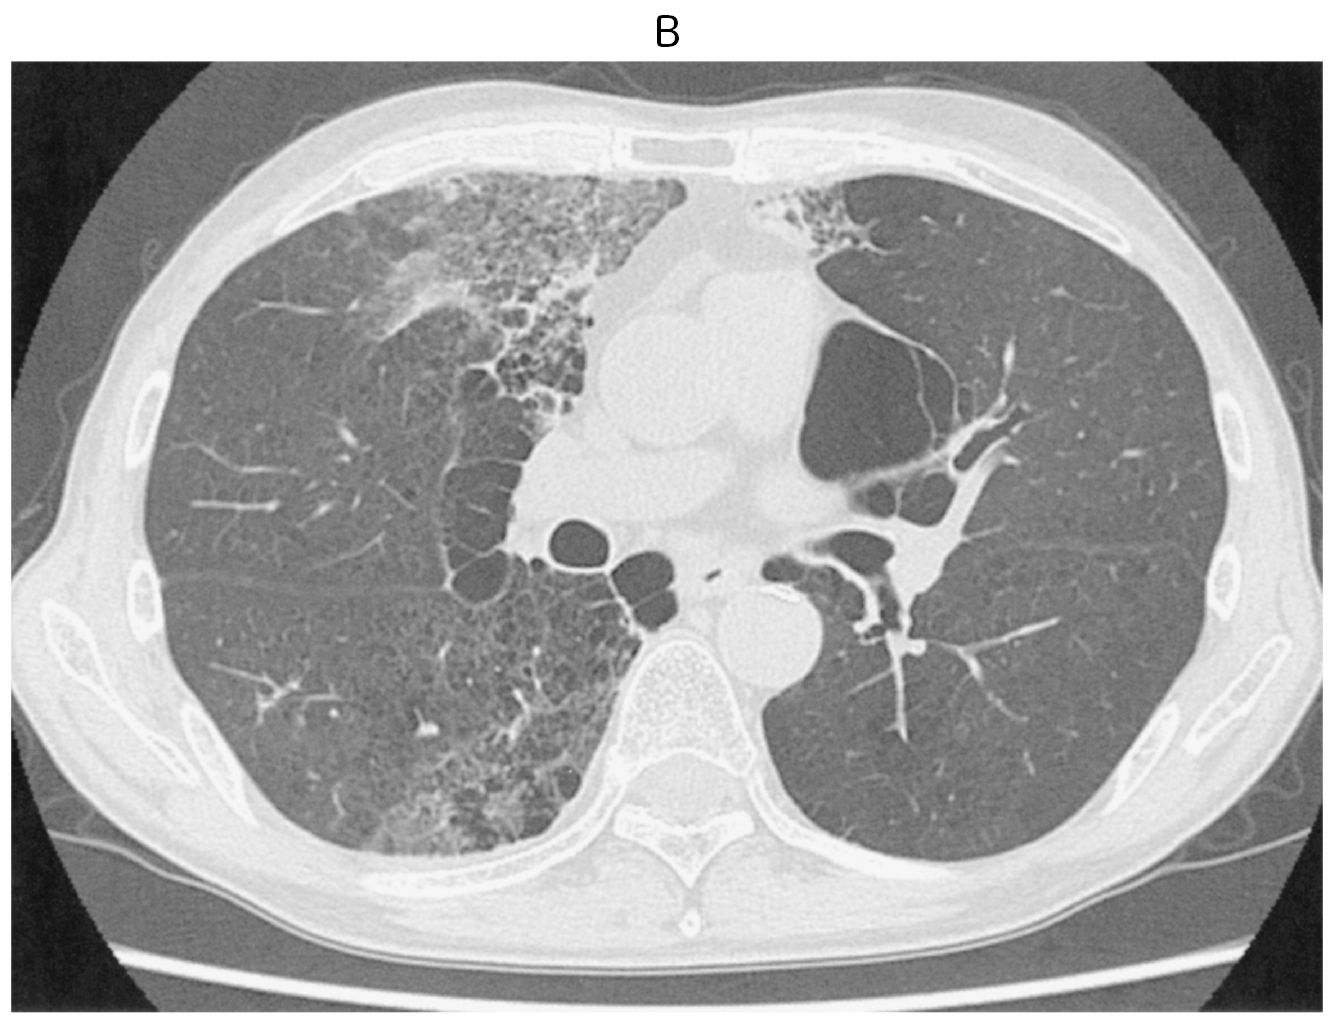

70歳の男性。1週間前からの咳と労作時の息切れを主訴に来院した。3か月前に肺小細胞癌(病期ⅢA)と診断された。診断時,自覚症状はなく,すぐに化学放射線療法が開始され,放射線治療は予定通り終了した。外来で化学療法の継続が予定されている。既往歴に特記すべきことはない。喫煙歴は30本/日を50年間。飲酒は機会飲酒。石綿などの粉塵吸入歴はない。意識は清明。身長170cm,体重62kg。体温36.5℃。呼吸数16/分。SpO2 90%(room air)。右胸部にfine cracklesを聴取する。血液所見:赤血球468万,Hb 13.9g/dL,Ht 42%,白血球7,800(分葉核好中球52%,好酸球2%,単球6%,リンパ球40%),血小板21万。血液生化学所見:LD 280U/L(基準124~222),BNP 10pg/mL(基準18.4以下)。免疫血清学所見:CRP 1.0mg/dL,β-D-グルカン2.2pg/mL(基準10以下)。胸部CT上の線量分布図(A)と受診時の胸部単純CT(B)とを下に示す。